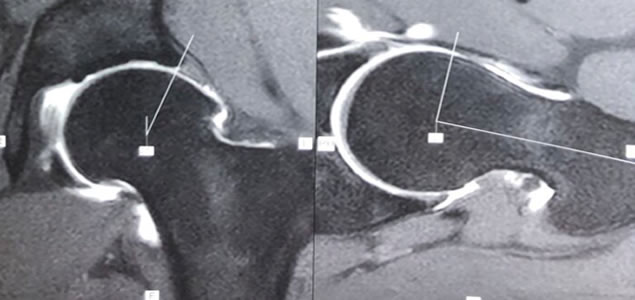

El Síndrome de Fricción Femoroacetabular (FFA) es una alteración en el funcionamiento articular caracterizado por una tríada de síntomas, signos clínicos y hallazgos imagenológicos que representan una sintomática y prematura fricción entre el fémur y el acetábulo (secundario a un trastorno en la forma de alguno de ellos o ambos) en determinados rangos de movimiento de la cadera, principalmente en flexión y rotación interna.

El trastorno morfológico puede ser de causa acetabular (Pincer) y consiste en una alteración en la orientación o profundidad de la cavidad acetabular; o la deformidad puede ser de origen femoral (cam) existiendo una anesfericidad o prominencia ósea en la región anterosuperior de la unión cabeza-cuello femoral.

La artroscopía de cadera es una interesante herramienta quirúrgica para solucionar patologías del Labrum acetabular, lesión condrales y corregir trastornos friccionales de la articulación, mediante incisiones mínimas y con buenos resultados reportados en la literatura.